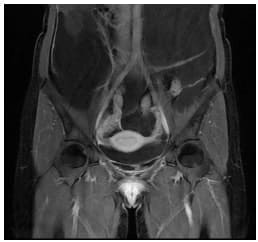

Se realizó una resonancia magnética de abdomen y pelvis que demostró la ocupación de todos los recesos peritoneales con líquido complejo de diferentes captaciones y septos multiloculados, la ocupación del espacio subfrénico derecho debido al desplazamiento tanto del hígado en sentido superior, como de las asas intestinales incluyendo el colon derecho en sentido central y en sentido posterior rechazando el colon descendente. No había compromiso retroperitoneal.

Se encontró además una lesión quística dominante adyacente al pedículo ovárico derecho sin conformarse propiamente una masa ovárica, lo que hizo sospechar el origen en la trompa.

Debido a la presentación clínica y a los resultados de la resonancia, se sospechó un pseudomixoma peritoneal de probable origen apendicular (Figuras 1-3).

Figura 2. Resonancia magnética abdominal en corte T1 con supresión grasa post contraste

(corte coronal). Se observa la primera lesión quística en la trompa derecha.